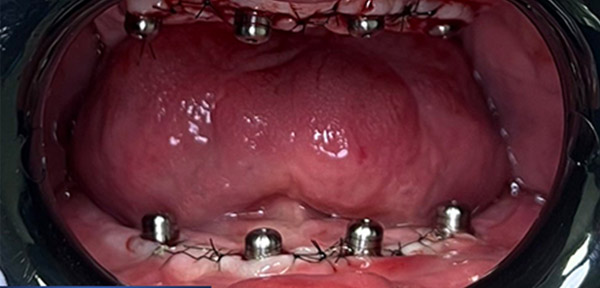

Transformările pe care le-am realizat. Cazuri clinice care reflectă precizia, experiența și dedicarea noastră.

Vezi cum pacienții noștri și-au recăpătat dantura fixă și funcționalitatea cu ajutorul implantologiei dentare moderne la Clinica Evodent Timișoara.